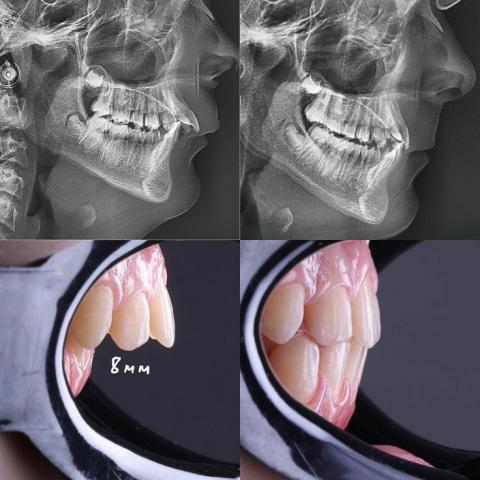

8mm Overjet Case Review: Full Analysis, Treatment Plan, and 14-Day Correction Timeline

1. Cephalometric Findings

The X-ray images show a sagittal discrepancy consistent with:

The upper front teeth appear to be leaning forward, creating an 8mm anterior overjet (as labeled in the clinical photo).

This significantly affects lip support, facial profile, and function.

Mildly convex profile indicating possible Class II skeletal pattern.

Chin position appears slightly retruded relative to the upper jaw.

The dental protrusion (teeth forward) is more pronounced than skeletal imbalance, suggesting a dental Class II Division 1 malocclusion.

No sign of fractures, pathology, or bone anomaly visible on the cephalometric scan.

2. Clinical Intraoral Observation

(From lower two images)

A. 8mm Positive Overjet

Normal overjet: 2–3 mm

Client has: 8 mm, classified as moderate to severe